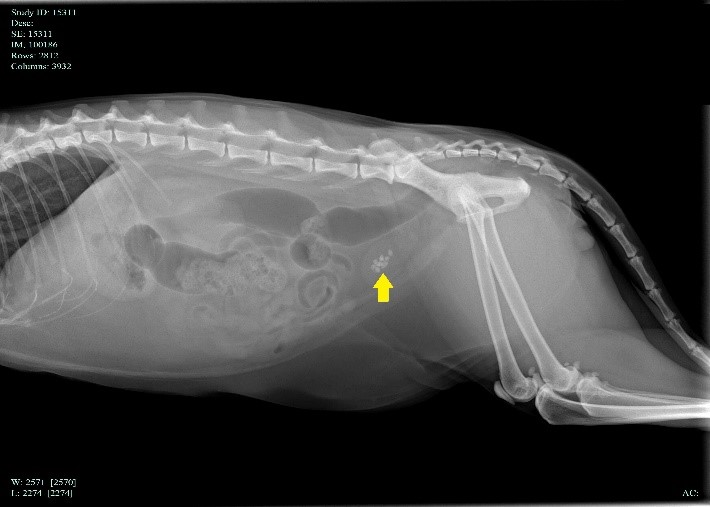

اين علائم باليني را مي توان در ساير بيماري هاي مجاري ادراري (مثلاً عفونت يا تومور) نيز مشاهده کرد ، بنابراين تشخيص سنگ ادراري بايد با اشعه ايکس يا سونوگرافي تأييد شود.

با اخذ يک شرح حال کامل و معاينه فيزيکي توسط دامپزشک شک به وجود سنگ و يا کريستال ادراري ايجاد و با انجام رادیوگرافي و يا سونوگرافي تاييد مي گردد. سپس آزمايش خون و ادرار نيز مي تواند جهت روند درمان کمک کننده باشد.